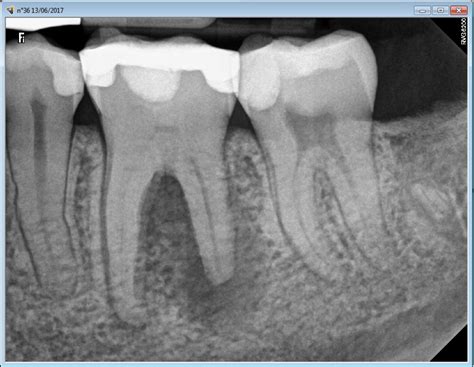

If you suspect that you have root canal calcification, it is important to seek dental care promptly. Your dentist may use X-rays or other imaging techniques to confirm the diagnosis and determine the extent of the calcification. From there, they will recommend an appropriate treatment plan.

If you are experiencing any of the symptoms mentioned above, it is essential to visit your dentist for a proper diagnosis. The diagnosis of root canal calcification is usually made through a dental examination and X-rays of the affected tooth. In some cases, your dentist may also perform a pulp vitality test to assess the health of the tooth's nerves.

Root canal calcification is usually diagnosed through a combination of clinical examination and dental imaging techniques such as X-rays, CT scans or cone-beam computed tomography (CBCT). These imaging techniques can provide dentists with a detailed view of the internal structure of the tooth and help identify any areas of calcification or other abnormalities.